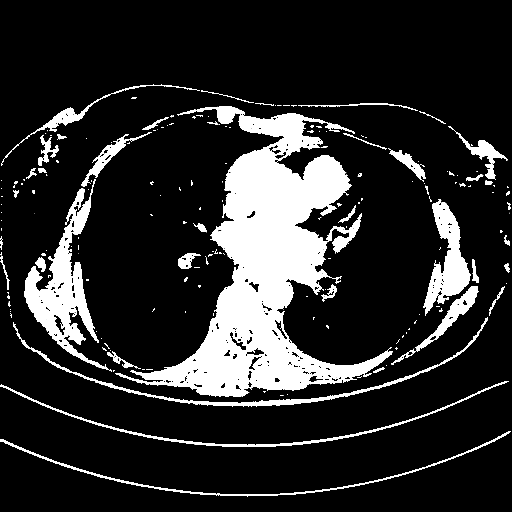

Original VENOUS CT scan

Full window (WL 1023.5, WW 4095 β†’ Low βˆ’1024, High +3071)

Actual HU range: [-1024.0, 3071.0]